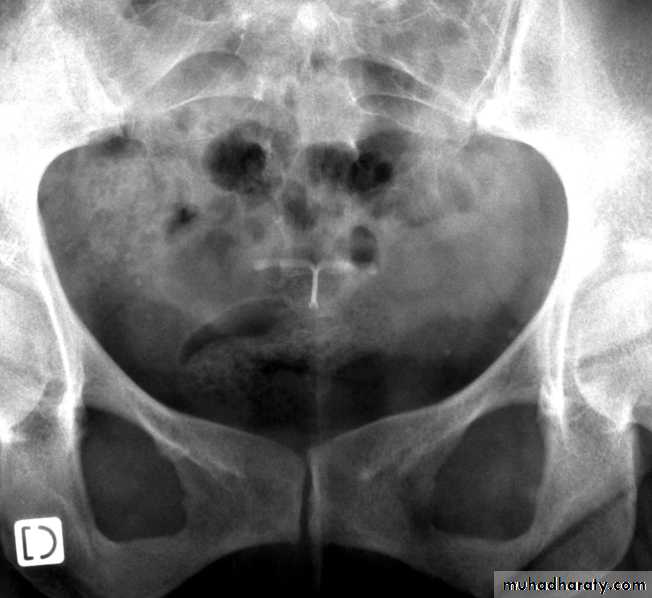

Ultrasound imaging

Copper IUD

LNG IUD